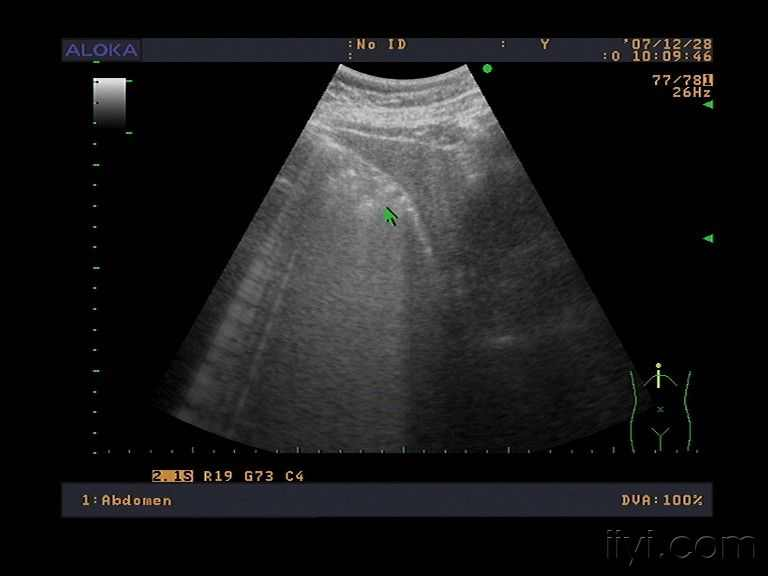

萎缩性胆囊炎属于消化系统良性疾病,是指因胆囊结石伴慢性胆囊炎反复炎症刺激所致胆囊整体解剖结构缩小,胆囊组织由于长期慢性炎性增生纤维化或形成瘢痕,胆囊壁明显增厚,组织解剖层次消失,胆囊逐渐萎缩并失去浓缩泄胆汁功能。萎缩性胆囊炎多数表现为反复发作右上腹痛,上腹部不适,慢性消化不良、厌油腻食物等症状。确诊萎缩性胆囊炎主要依靠肝功能检查、超声检查、磁共振胰胆管成像、CT扫描、静脉胆道造影等检查。早期可酌情给予药物治疗,但由于萎缩性胆囊炎病程较长,且反复发作,存在较高恶变率,非手术疗法难以治愈,因此一旦确诊选择手术治疗是最佳方案。胆囊切除术后可完全消除症状。